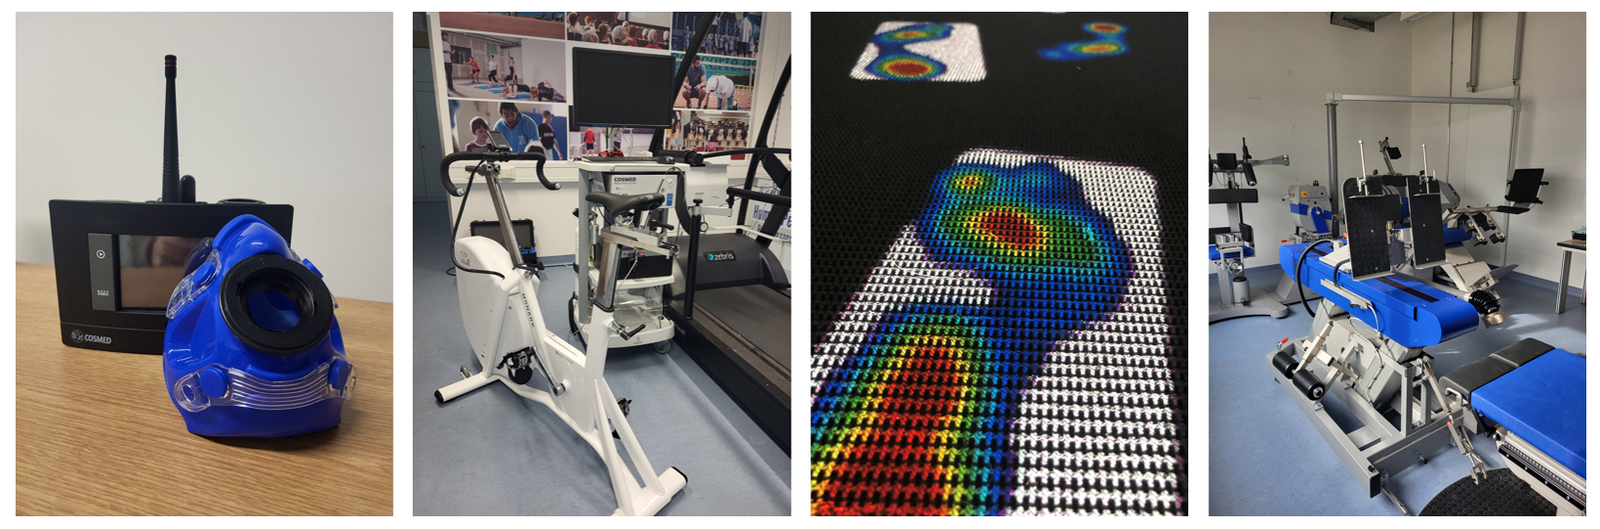

Die Spirometrie ist ein Verfahren zur Diagnostik der Lungenfunktion eines Menschen. Messbare Parameter wie der Tiffenau-Index und Vitalkapazität werden zur Differenzierung obstruktiver (z. B. Asthma bronchiale) und restriktiver Lungenerkrankungen (z. B. Lungenfibrose) verwendet. Als Ergänzung zur stationären Spirometrie-Einheit ist im Zentrum für Leistungsdiagnostik und Sportmedizin auch ein mobiles Spirometrie-Gerät (COSMED Srl, Albano Laziale, Italien) vorhanden.

Die Spiroergometrie dient der Untersuchung des Herz-Kreislauf-Systems, der Lungenfunktion sowie des Energiestoffwechsels unter Belastung. Bei der Spiroergometrie werden die Atemgase gemessen und der kardiologische Zustand des Probanden während einer Belastung überwacht. Im Zentrum für Leistungsdiagnostik und Sportmedizin stehen dabei ein Laufband, Ergometer-Fahrrad sowie ein mobiles 12-Kanal-EKG zur Verfügung. Bei der Leistungsdiagnostik werden ebenfalls Laktatwerte zur Erstellung optimaler Trainingspläne von Sportlern verwendet.

Das Laufband des Zentrums für Leistungsdiagnostik und Sportmedizin ist mit einem visuellem Schrittvorgabesystem ausgestattet. Dies kommt hauptsächlich in der neurologischen, orthopädischen und geriatrischen Rehabilitation zum Einsatz. Das Gangbild des Probanden bzw. des Patienten wird automatisch erfasst. Dieses Schrittmuster wird je nach Zielvorgaben (z. B. Schrittlänge, Schrittweite und Fußwinkel) angepasst. Das Schrittmuster wird auf das Laufband projiziert und der Proband versucht dieses einzuhalten. Dadurch können Ganganomalien und die Gangsymmetrie verbessert werden.

Unter Pedobarographie ist die statische oder dynamische Untersuchung der Druckverteilung an der Fußsohle bei verschiedenen Aktivitäten des täglichen Lebens zu verstehen. Im Zentrum für Leistungsdiagnostik und Sportmedizin stehen zwei verschiedene instrumentelle Methoden zur Verfügung. Zum einen sind in der Lauffläche des Laufbandes Drucksensoren mit einer Sensorfläche von 162.6 cm x 54.2 cm (12288 Sensoren & Abtastrate: 100 Hz) integriert. Zum anderen werden OpenGo Sensorsohlen (Moticon ReGo AG, München, Germany) in den Schuhgrößen 36-47 für die Druckverteilungsmessung im Schuh verwendet.

Die Kraftmessung ist im Sportbereich sowie auch in der Mehrkörpersimulation sehr wichtig. Hierfür ist die OTH Weiden mit einem IsoMed 2000 (D. & R. Ferstl GmbH, Hemau, Deutschland) ausgestattet. Dieser ist für die Leistungsdiagnostik und für Training im Sport- und wissenschaftlichen Einsatz. Für den Probanden werden Trainingsziele festgelegt bzw. Untersuchungsprotokolle angelegt.